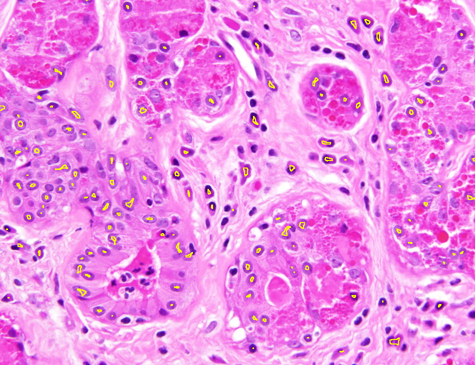

Dataset 1 comprises a synthetic video and two hematoxylin and eosin (H&E)-stained images collected from public online sources [71, 72]. H&E staining is standard in histopathology, with nuclei appearing blue–purple and cytoplasm pink. The images are provided in RGB format with varying image sizes and are used solely for qualitative illustration and timing comparisons, as no ground-truth annotations are available. The synthetic video consists of 74 MATLAB-generated frames. The first frame shows a 3D mitochondrial mesh generated via the isosurface function and rendered with Phong illumination, with the light source positioned above and to the right of the camera. Subsequent frames are obtained by rotating this initial view. This dataset was constructed to study segmentation under pronounced frame-to-frame illumination changes.

Representative samples from the three datasets are shown in Fig. 1. In (a), the first frame of the synthetic video in Dataset 1 illustrates the strong illumination gradients produced by distance-dependent shading together with orientation-dependent interactions between vertex normals and the light direction. The H&E images in (b) and (c), also from Dataset 1, depict a mast cell infiltrate from a patient with non-alcoholic steatohepatitis and cirrhosis and, respectively, a sample from a patient with sclerosing polycystic adenosis of the parotid gland; the former consists primarily of purple nuclei, white cytoplasm, and pink extracellular tissue. Subfigures (d) and (e) show two examples from Dataset 2 accompanied by their ground-truth nuclei annotations, while (f) and (g) present a representative image from Dataset 3 together with its corresponding cell mask.

Figure 1: Samples from Datasets 1–3. (a) First frame of the 74-frame video in Dataset 1 (1770 × 880) with a superimposed red mesh. (b,c) H&E-stained tissue images from Dataset 1 (1000 × 750; 950 × 730). (d,e) Cell images from Dataset 2 (600 × 600) with nuclei annotations. (f,g) Image from Dataset 3 (512 × 512) with annotation.